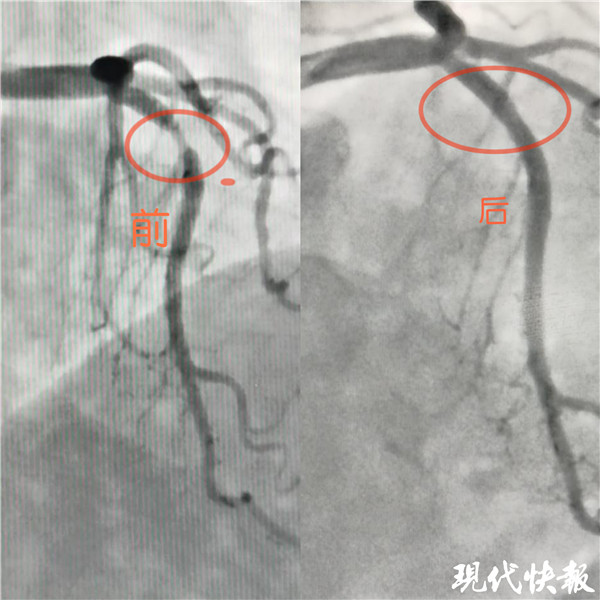

記者了解到,入院后完善冠狀動(dòng)脈造影檢查示,張女士LM正常,LAD近段血管90%狹窄, LCX及RCA未見(jiàn)狹窄。淮安市一院心內(nèi)科介入治療團(tuán)隊(duì)嚴(yán)格把握適應(yīng)癥,和患者及家屬溝通后,于LAD病變處植入一枚藥物可吸收支架,術(shù)后血管內(nèi)超聲檢查提示支架貼壁良好。